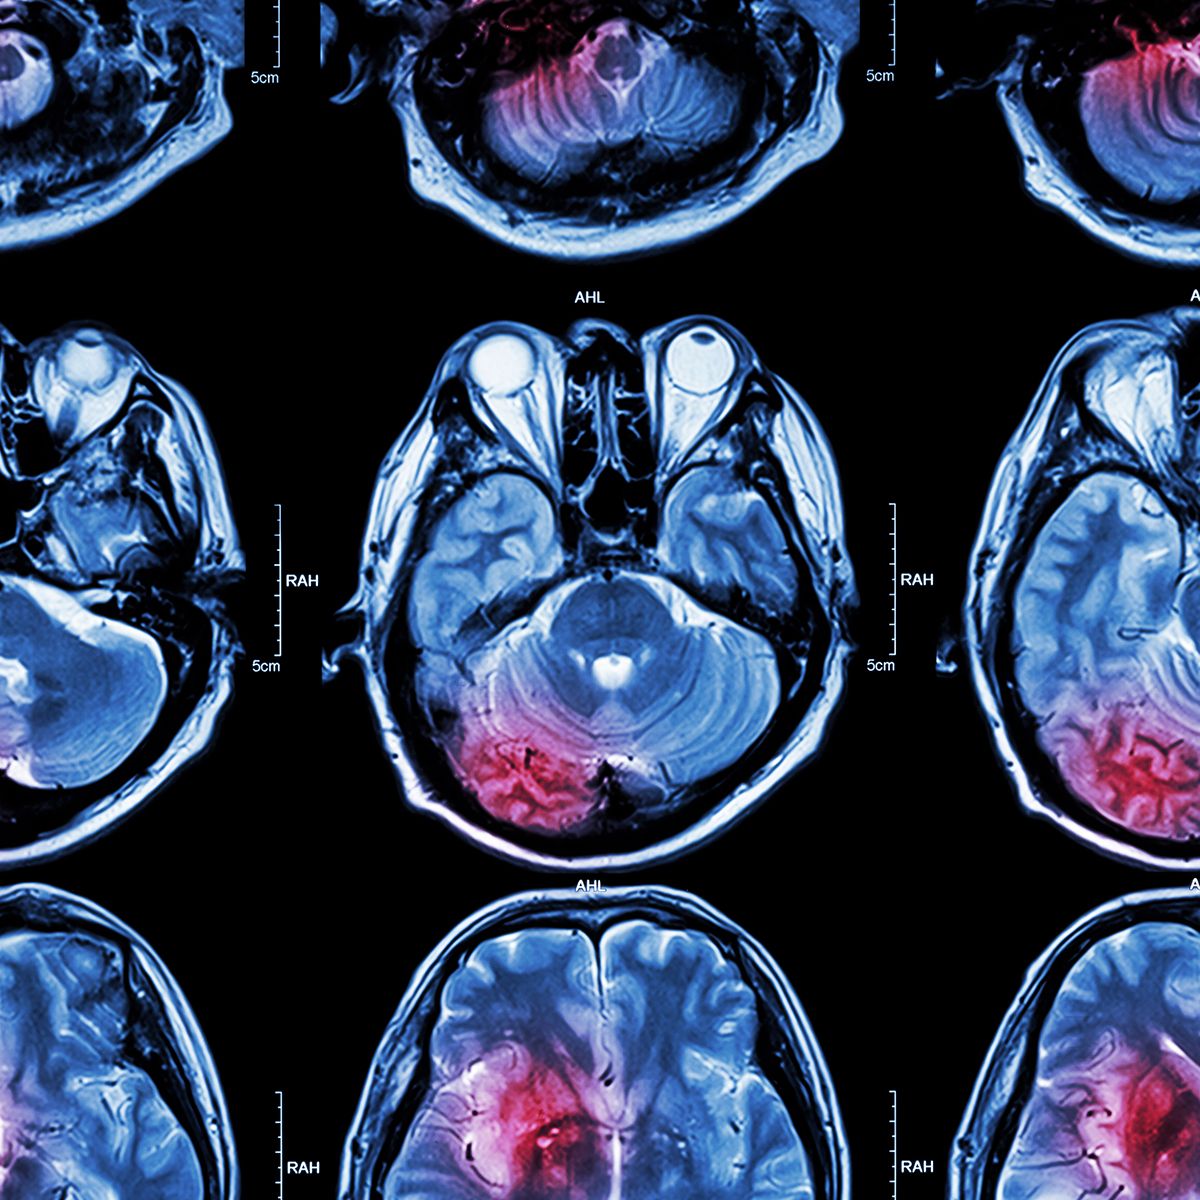

Trying the "Kitchen Sink" to treat Brain Cancer

There are a number of treatment methods being explored to treat glioblastoma.